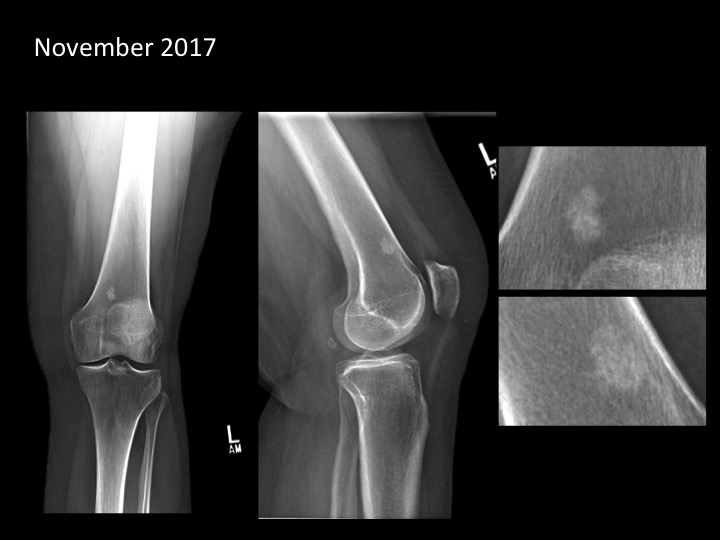

60 year old woman with knee pain

Figure 1 for case bone island ( RID4004 )

Figure 1